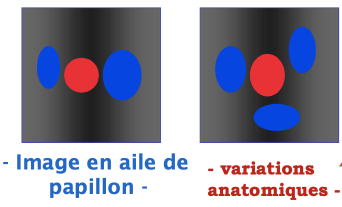

Veine poplitée

Veine poplitée